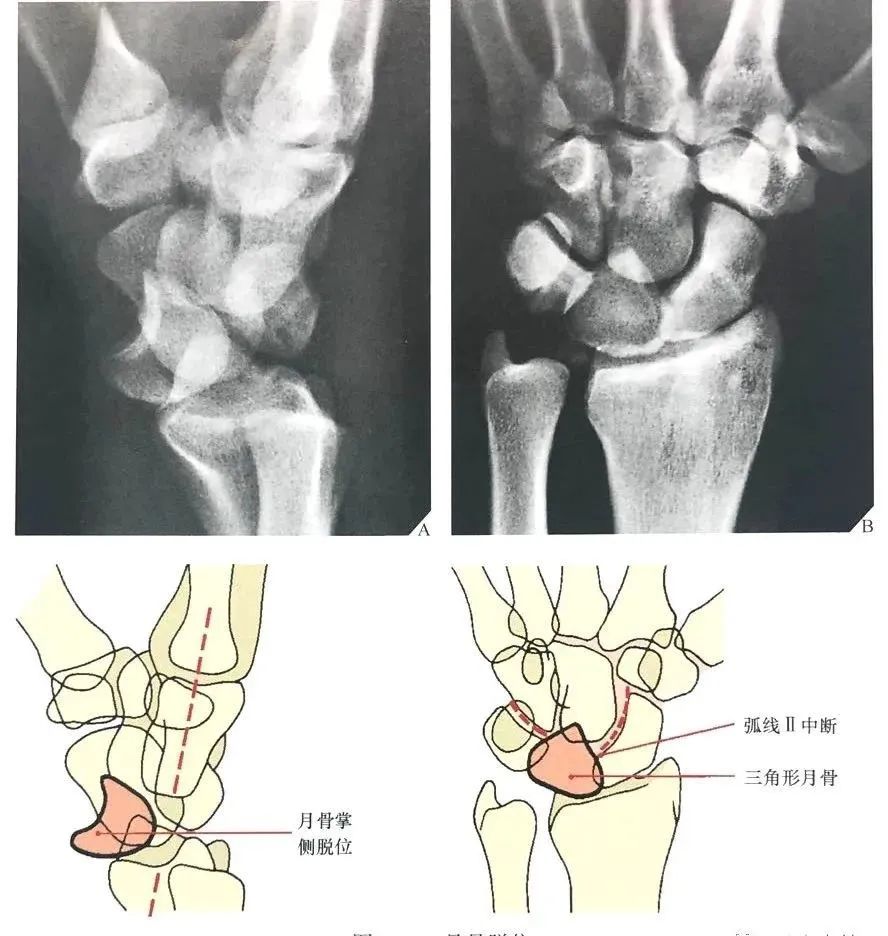

图21 左:月骨脱位;右:月骨周围脱位

月骨和月骨周围脱位:腕关节中立位置的背掌位和侧位X线片足以诊断月骨和月骨周围脱位。侧位像可以清晰显示在桡骨远端上方的月骨、头状骨和第三掌骨长轴呈直线状排列,这条线任何一点的中断都能确定半脱位或脱位的诊断。

当头状骨保持在直线上,一旦月骨成角度离开桡骨远端表面,月骨脱位即可被识别(图22A)。

同样的,在背掌位投照时,由舟骨远端凹面、月骨、三角骨所构成的弧线 II 的中断和相伴随的月骨三角形外观也可以诊断月骨脱位(图22B), 月骨脱位也能有效地从CT上显示,尤其是3D CT的重建图像(图23)。

图22 月骨脱位。(A)在腕关节侧位像上,月骨脱位时脱离由第三掌骨、头状骨和桡骨远端的长轴排列,月骨向掌侧旋转和移位。(B)背掌位投照显示弧线 II 在月骨位置中断。注意月骨的三角形外观及月骨脱位的征象。

在腕关节侧位片上,一旦头状骨长轴骨偏离月骨和桡骨远端表面所形成的直线而向背侧成角或掌侧成角,即可诊断月骨周围脱位。

月骨周围脱位时虽然月骨半脱位造成一定程度的月骨倾斜角,但月骨仍保留在与桡骨远端表面所形成的关节内(图24A)。

在背掌位片上,腕骨的近侧列和远侧列重叠、弧线 II 和弧线 Ⅲ 在头状骨的位置中断,提示月骨周围脱位(图24B)。

图24 月骨周围脱位。(A)腕关节侧位X线片显示典型的相对于月骨的头状骨背侧移位,虽然月骨轻度掌侧旋转,但仍保留在与桡骨远端所形成的关节内。注意第三掌骨、头状骨与月骨和桡骨远端所形成的直线中断。在背掌位投照X线片上(B),月骨周围脱位表现为由弧 II 和弧 Ⅲ 的中断所造成的腕骨近侧列与远侧列的重叠。